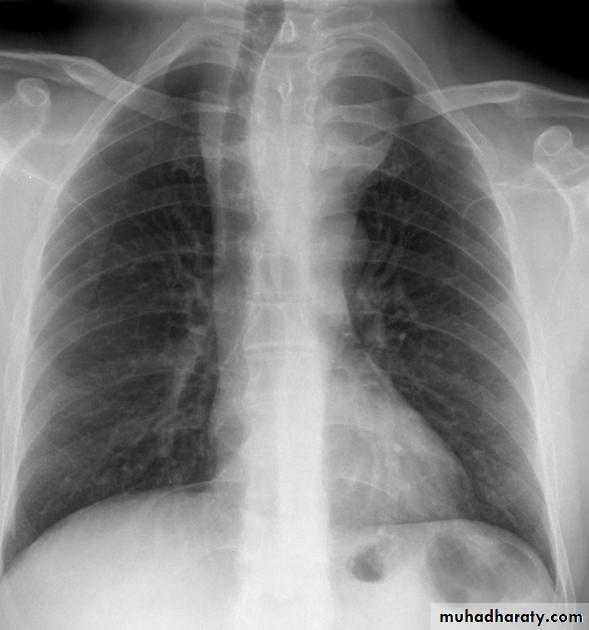

Hodgkin lymphoma of te middle mediastinum